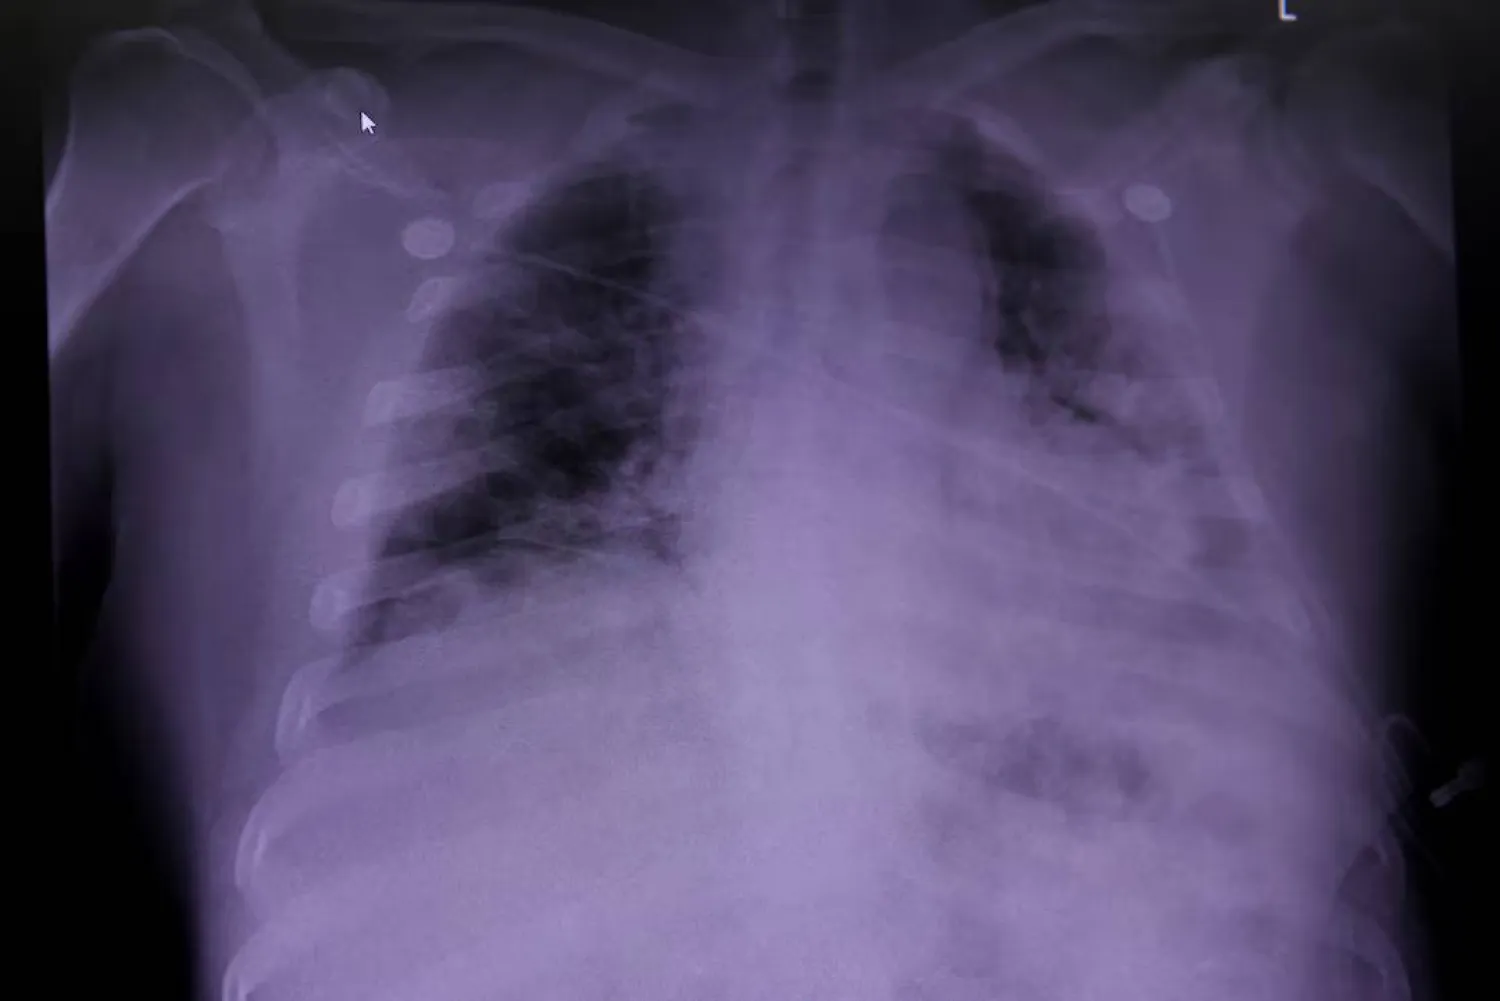

ويحذّر الباحثون بأن تشخيص سرطان الرئة غالباً ما يحدث في مراحل متأخرة بعد ظهور الأعراض؛ مما يقلل فرص العلاج. وتؤكد الباحثة لوري ساكودا، على ضرورة تغيير التصورات العامة والتوعية بأن أي شخص قد يصاب بسرطان الرئة، بغض النظر عن تاريخه مع التدخين.

حالياً، تقتصر توصيات الفحص على التصوير المقطعي منخفض الجرعة لمن هم بين 50 و80 عاماً ممن لديهم تاريخ تدخين كبير. ومع ذلك، لا يتجاوز معدل الالتزام بالفحص 15 في المائة بين المؤهلين، كما أن شركات التأمين غالباً ما تغطي الفحص فقط ضمن المعايير الرسمية. أما الفحوصات الشاملة للجسم، فهي غير موثوقة للكشف عن سرطان الرئة وقد تعرّض المرضى للإشعاع وتكلف مبالغ مرتفعة.

أعراض سرطان الرئة متشابهة لدى المدخنين وغير المدخنين، وتشمل السعال المستمر، وسعال الدم، وألم الصدر المتكرر، وضيق التنفس، والصفير. لكن غير المدخنين قد لا يتوقعون إصابتهم؛ مما يؤخر مراجعتهم الطبيب. وينصح الأطباء بأخذ هذه الأعراض بجدية إذا استمرت لأسابيع.